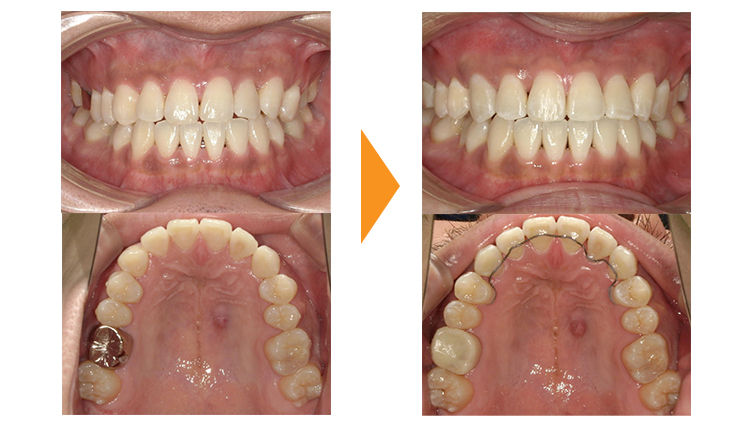

治療期間の問題や、高校生で進学による通院が困難になる可能性もあり、ご本人の希望されていたすきっぱ(正中離開)を部分矯正で治療した症例です。

インビザラインでの治療も可能な症例ですが、ワイヤー矯正の方が治療開始が早くできる点や、インビザラインではコストがかかりすぎるためワイヤー矯正を選択されました。インビザラインはスキャンから発注・治療計画の修正・郵送といった手続きがあるため1か月以上は治療開始まで日数を要します。

ワイヤーであればその日に装置を付けることも可能ですので、今回のような治療期間が4か月と短い場合には、インビザラインで失う1か月はかなり大きなデメリットとなります。

またインビザラインの場合、先ほどのように前歯6本に矯正器具を装着するケースと、今回のように前歯2本のみ矯正器具を装着するケースで費用が同じであることが多いです。ワイヤー矯正の場合は器具の数に応じて費用が変わることも多く、当院でも器具の数は治療期間の目安によって価格が変わります。

すきっぱは後戻りがしやすい歯並びなので、矯正後は歯の裏側からワイヤー固定を使用し、マウスピースも継続して使用していただいています。

この患者様は前歯2本に矯正器具を装着し、動かす量も少なかったため短期間で矯正治療が終了することができました。

| 初診時 | 16歳女性 |

|---|---|

| 主訴 | すきっぱが気になる |

| 期間 | 約4か月 |

| 矯正 | ワイヤー矯正 |

| 費用 | 基本検査22,000円・契約料110,000円・調整料5,500円/月(税込) |

| 治療上のリスク | 歯磨き不良の場合はむし歯になる可能性。 習癖に伴う後戻りの可能性。 |